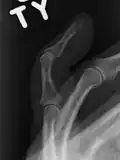

Diagnostic methodBased on symptoms, X-rays[3]

A mallet finger usually results from overbending of the finger tip.[3] Typically this occurs when a ball hits an outstretched finger and jams it.[3] This results in either a tear of the tendon or the tendon pulling off a bit of bone.[3] The diagnosis is generally based on symptoms and supported by X-rays.[3]

The diagnosis is generally based on symptoms and supported by X-rays.[3] The injury can be accompanied by swelling and ecchymosis.[4]